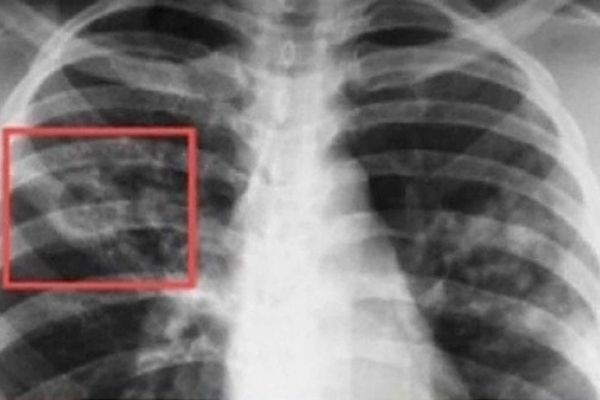

Нещодавно у Здолбунові виявили туберкульоз в учня місцевої гімназії. Під час планового огляду у старшокласника лікарі встановили бацилярну, тобто відкриту, із виділенням мікобактерій, форму туберкульозу. Про це повідомляє Радіо Трек.

Всі інші діти, які навчаються у закладі, здорові. Наразі хворий перебуває на лікуванні, а в навчальному вжили заходів, аби запобігти можливому поширенню захворювання.